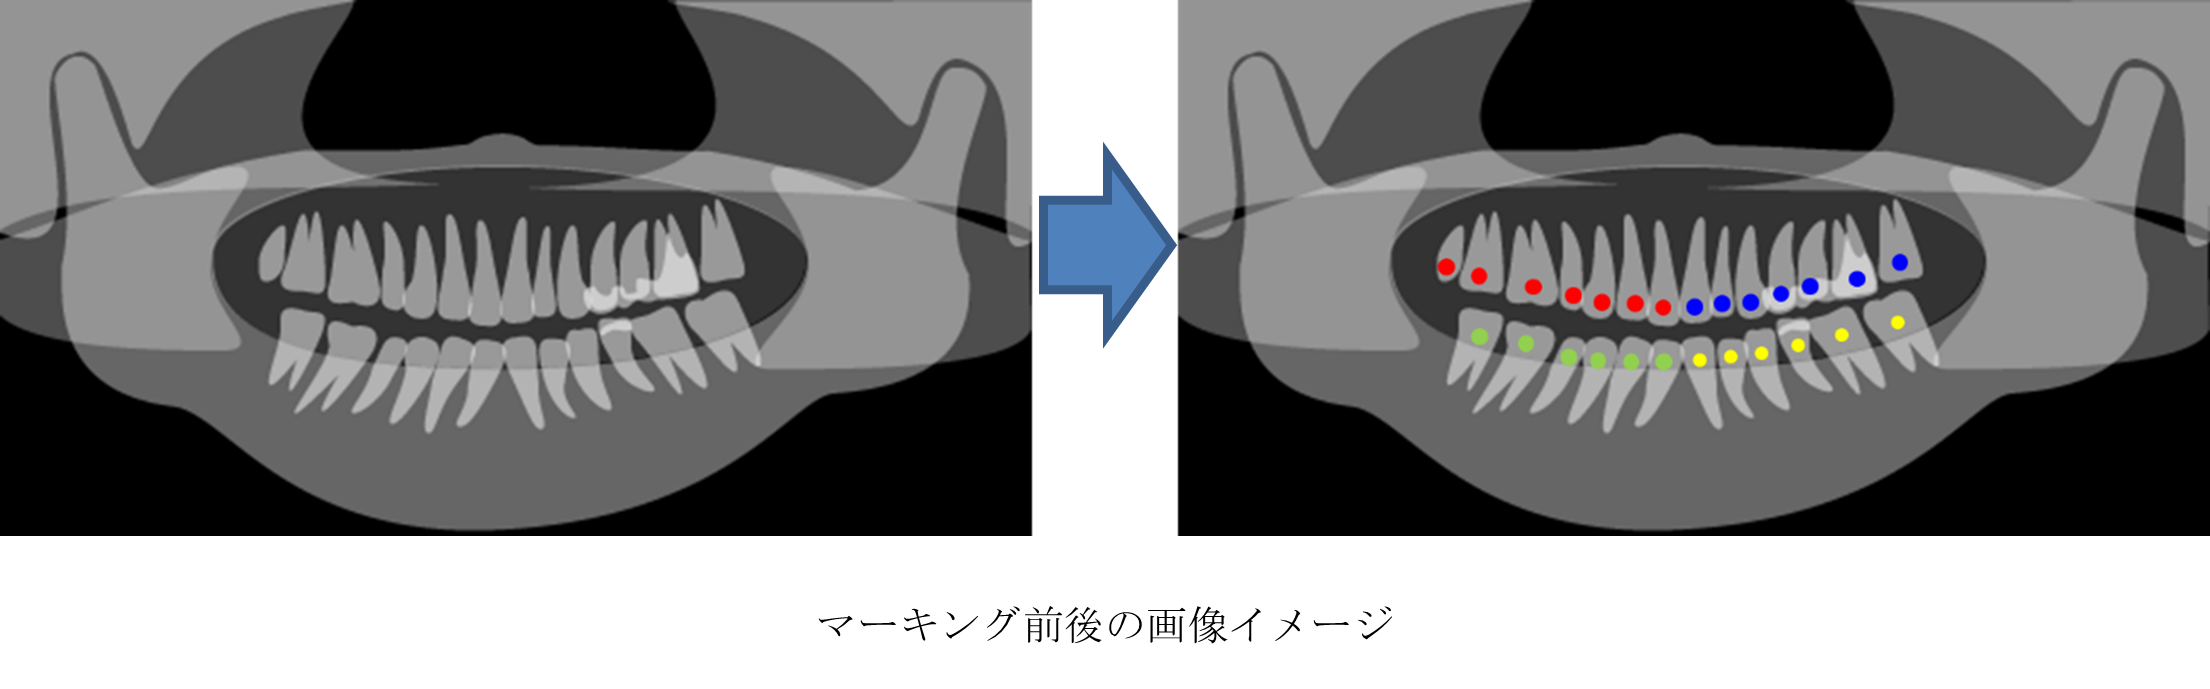

(1)マーキング

歯の上下左右の位置で色分けされたマークを付与するよう学習させた機械学習モデルを使用して、パノラマレントゲン画像上にマーキングします。

最初にマーキングすることで、後段のナンバリングや、画像切り出しの精度を高めることができます。また、色分けしたマーキングにより、必ずしも画像の中央にあるとは限らない、歯列の中央を容易に識別することができます。さらに、本フローのデータは、そのまま本機械学習モデルの学習データとして活用できます。